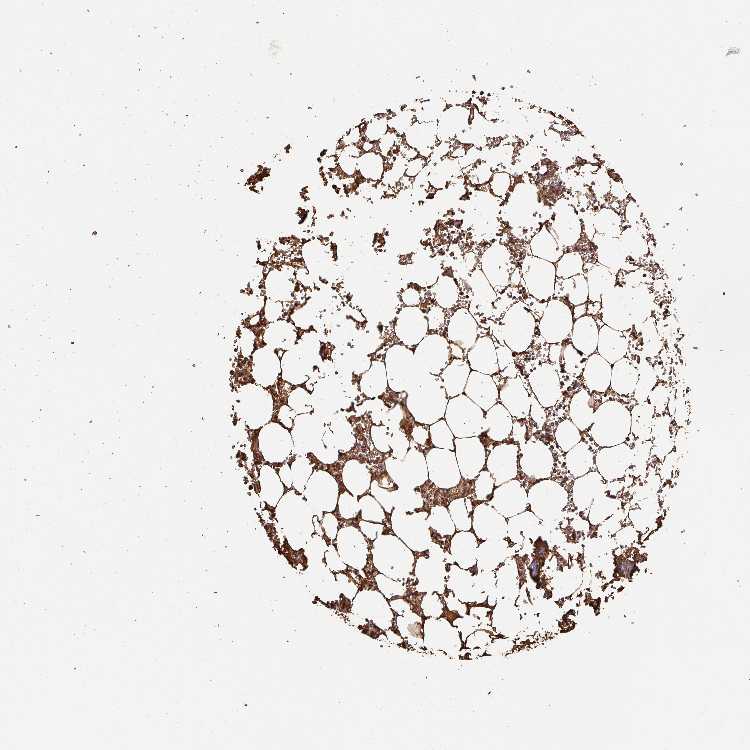

BONE MARROW - Antibody stainingi

Antibody staining in the annotated cell types in the current human tissue is reported as not detected, low, medium, or high, based on conventional immunohistochemistry profiling in selected tissues. This score is based on the combination of the staining intensity and fraction of stained cells.

Each image is clickable and will lead to virtual microscopy that enables deeper exploration of all samples and also displays staining intensity scores, fraction scores and subcellular localization as well as patient and tissue information for each sample.

Antibody HPA031024Antibody HPA031025Antibody CAB006262

Hematopoietic cells LowMediumLow